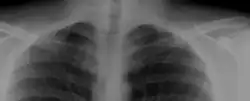

Bilateral, symmetric, full, ossified cervical ribs.

On imaging, cervical ribs can be distinguished because their transverse processes are directed inferolaterally, whereas those of the adjacent thoracic spine are directed anterolaterally.[16]